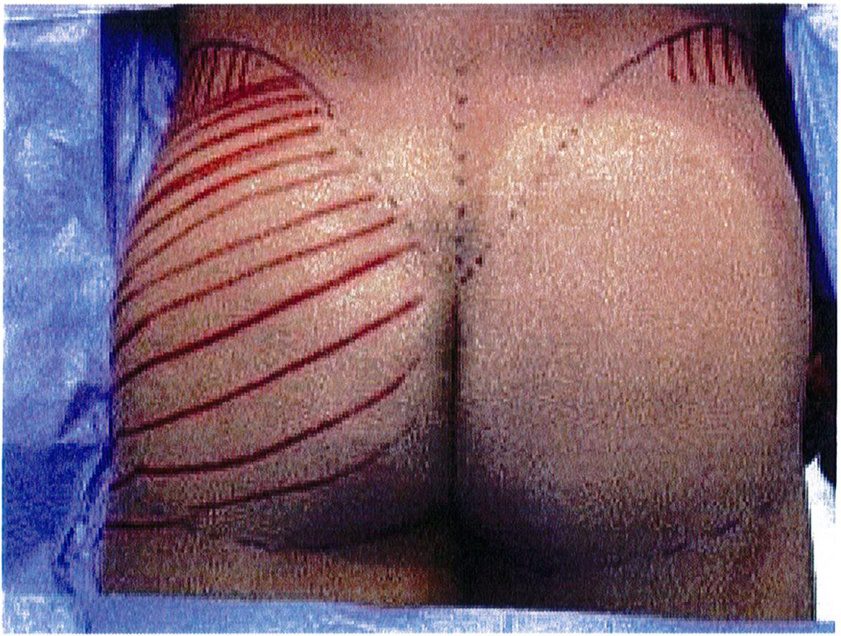

Hình. 2. Vị trí xuất chiếu của lớp cân mạc trên da kèm theo hướng đi của chúng. (Trích từ de la Pena JA, Rubio OV, Cano JP, et al. Subfascial Gluteal Augmentation. Clin Plast Surg 2006;33:408; đã xin phép trước khi đăng tải.)

Lớp cân mạc bao phủ vùng mông tiếp giáp phía ngoài với lớp hạ bì. Chúng hoạt động như một hệ thống kết dính da và các tổ chức sâu dưới da với nhau. Hình 2 cho thấy vị trí lớp cân mạc xuất chiếu trên da và chiều hướng tương ứng